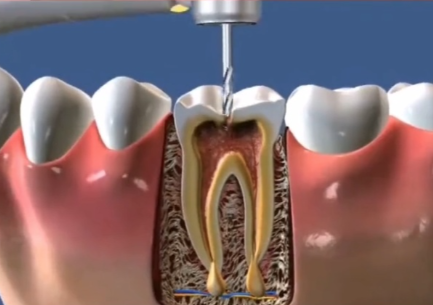

10. 根管治疗:500 - 2000元